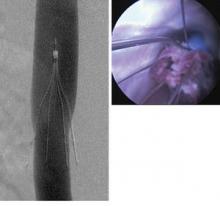

When Dr. Lazar Greenfield invented the filter in the early 1970s, it was intended to be used in patients at risk of a pulmonary embolism, but who had contraindications to anticoagulation therapy. Since that time, however, off-label use has expanded and filters proliferated. Now there are more than a dozen on the market, all approved by the FDA’s 510(k) process."In 2010, about 210,000 of these filters were deployed worldwide, but 85% of those were done in the U.S.," said Dr. Johnson, a professor of radiology and surgery at the Indiana University School of Medicine, Indianapolis, and a member of SIR. "In the best interest of our patients, this study will provide a systematic, functional view, repre- sentative of most filters placed in the United States. It will assist with quality improvement in filter placement, management, and retrieval."